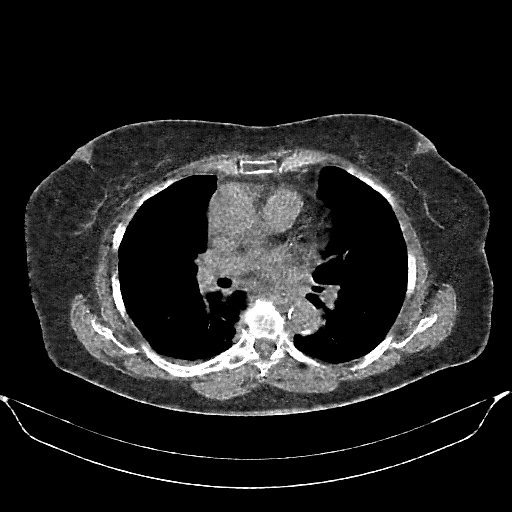

Generated VENOUS CT scan (A→B translation)

Full window (WL 1023.5, WW 4095 β†’ Low βˆ’1024, High +3071)

Lung window (WL -600, WW 1500 β†’ Low βˆ’1350, High +150)

Mediastinum window (WL 40, WW 400 β†’ Low βˆ’160, High +240)